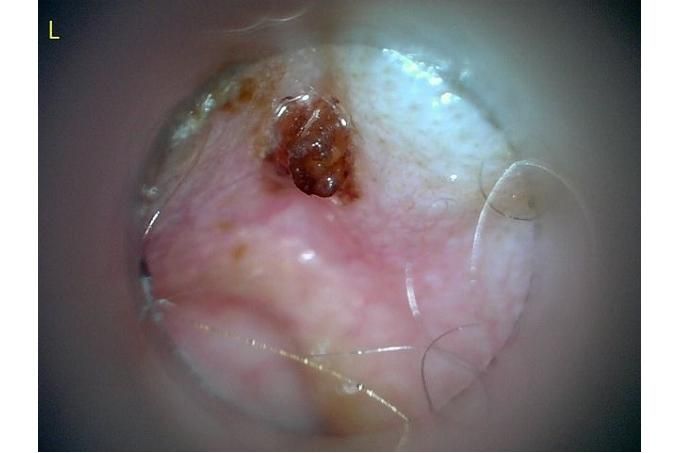

그리고 용종이라고 코멘트 달아주셔서 저 검이경 사진 찍은곳에 물어보니 용종은 아니라고합니다.

저 부분 용종 아니라합니다

제가 가장 알고싶은점은. 저렇게 옷깃에 귀가 시쳐도 아파할정도면 이게 외이염일까요 중이염일까요 내이염일까요? 얼마나 아픈지 옷한번 얇은 내복 평상시 입던거 입히면 입히고 나서 바로 온집을 돌아다니면서 바닥에 귀를 대고 정신나간애처럼 비비고 비틀비틀 걷습니다 그러다가 2~3분후 다시 정상으로 돌아옵니다